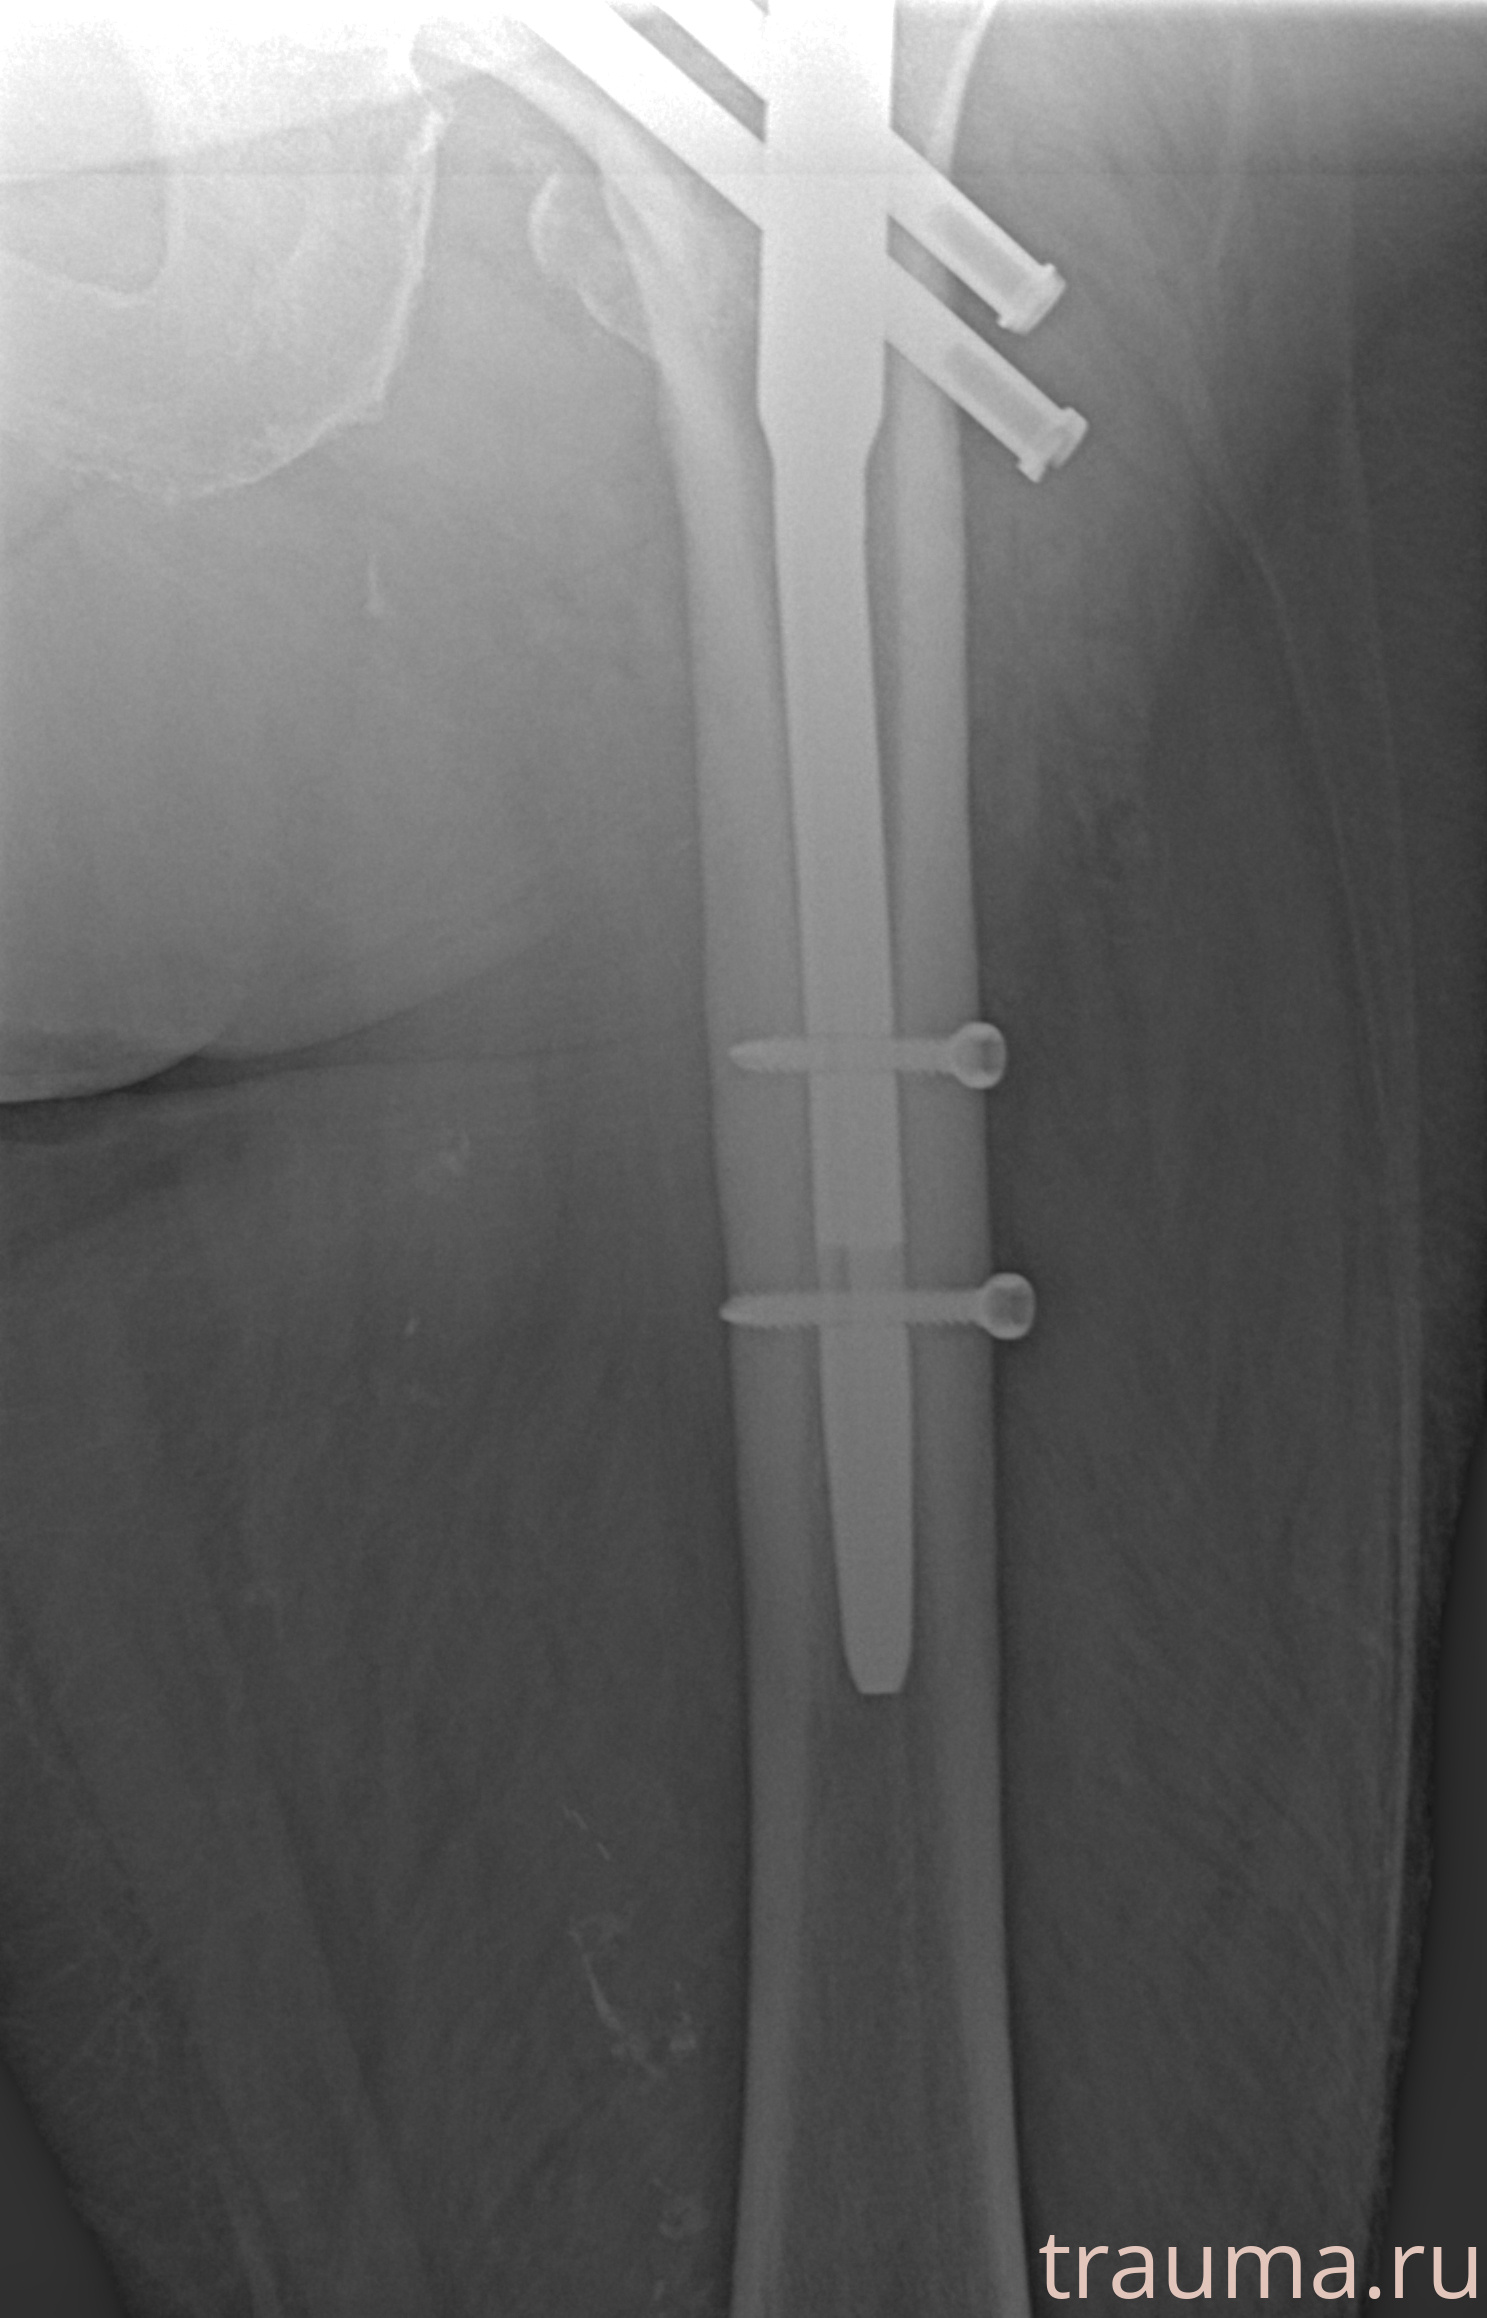

Рентгенограммы

Рентген на дому: по вашему адресу приезжает врач-рентгенолог, травматолог-ортопед с мобильным рентгеновским аппаратом, проводит диагностику травмы или заболевания, делает необходимые рентгенограммы, дает рекомендации по дальнейшему лечению. Получить качественные снимки в домашних условиях возможно благодаря уникальной методике, разработанной МосРентген Центром для института  Склифосовского